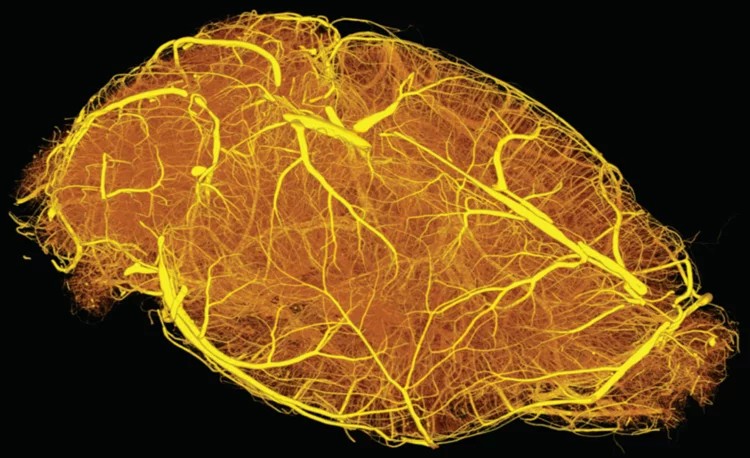

Hierarchical imaging and computational analysis of three-dimensional vascular network architecture in mouse brain

An international team involving researchers from the University and University Hospital Zürich, the Krembil Research Institute and the University and University Hospital in Toronto (Canada), the Department of Physics of Jyväskylä (Finland), the University of Leuven (Belgium), the Johannes Kepler University in Linz (Austria), the Novartis Institutes for Biomedical Research in Emeryville (USA), the ETH Zürich and the Paul Scherrer Institute has developed a protocol that enables hierarchical imaging and computational analysis of vascular networks in entire postnatal- and adult mouse brains, enabling direct and quantitative comparisons of the morphological brain vascular network architecture between different postnatal and / or adult developmental stages. The results have been published on Nature Protocols on September 3rd, 2021.